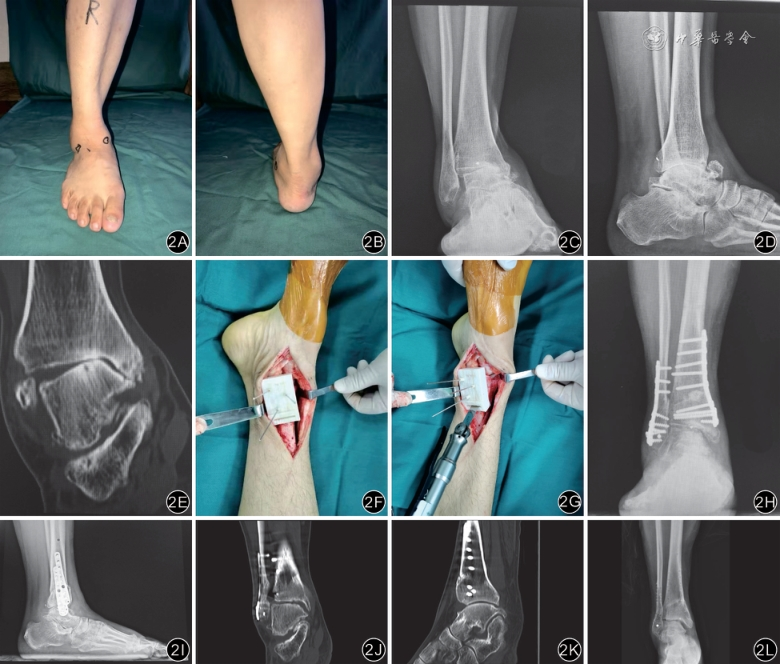

典型病例见图2。

手术方法:从切开皮肤至探查胫距关节面,步骤同对照组。安装截骨导板,使截骨导板与内踝完全贴合,打入3枚2 mm克氏针定位,50 mm摆锯沿导板上缘截骨槽截骨,保留截骨对侧骨膜及软组织。根据术前设计的撑开角度、距离及胫骨缺损大小,取相等髂骨,并修整成截骨端胫骨缺损形状。垫块填塞入截骨端,复位截骨端矫正踝关节力线。行C臂X线机透视确认踝关节力线、截骨位置良好。截骨端予钢板固定,正侧位透视检查无力线异常。部分畸形较重的患者如需进一步行腓骨截骨[8],术前于模型上模拟截骨,记录腓骨撑开的长度、截骨线的角度,在下胫腓关节近端处截骨,方向自外上向内下,复位纠正力线后,截骨端予植骨和腓骨钢板固定。

术前准备:根据患者术前CT三维重建资料打印1∶1踝关节3D标本。在踝关节负重位X线片上测量胫骨前侧关节面(tibial articular surface,TAS)角、胫骨侧面关节面(tibial lateral surface,TLS)角及TT角,并据此设计踝关节截骨导板。于3D假体上计算并绘制截骨线,在截骨线上设计导板上缘截骨槽,深度不可太深,防止损伤对侧骨膜及软组织,以50 mm摆锯全部进入时保留胫骨外侧骨皮质2~3 mm为宜(即摆锯据片50 mm,胫骨截骨线+导板厚度为52 mm),保留胫骨外侧合页结构。设计导板下缘与踝关节标本严格贴合,方便术中安装及定位。导板上预留定位孔,方便术中固定。于3D假体上模拟截骨,撑开胫骨内侧骨皮质,纠正踝关节畸形,于假体上测量胫骨内侧撑开的距离,便于术中测量取髂骨结构植骨的厚度。导板设计详见图1。